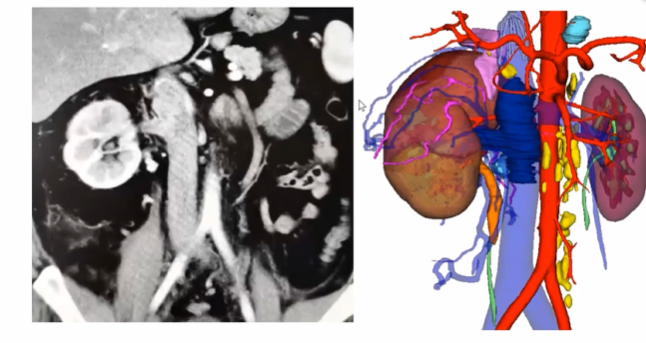

下腔静脉不一定都要阻断

对于腔静脉各端及分支的充分游离和暴露是顺利取栓的重要条件,而各支血管的完全阻断更为关键。但是,下腔静脉一定要阻断吗?既往积累经验告诉我们瘤栓上方下腔静脉完全不用阻断。如下图所示,病例患者具有肾静脉和肾上腺中央静脉双瘤栓,在手术中取肾上腺中央静脉的瘤栓时,其上方腔静脉并没有阻断,而是通过剪开腔静脉直接将瘤栓取出。取栓之后,再把静脉壁切掉,可以获得足够空间后再重新进行阻断,有利于完成后续缝合等多个操作。(备注:视频中有动态手术操作过程)